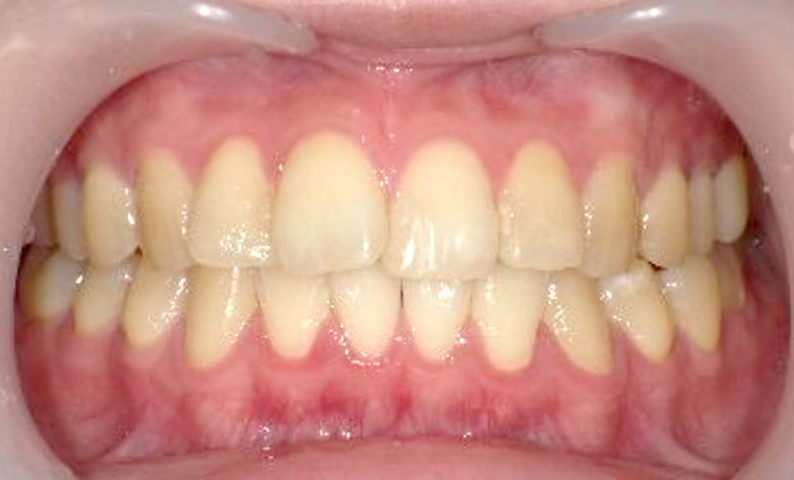

症例_001 前歯「捻転歯」症例

治療期間:6ヶ月金額:48万円+税20代女性少しのねじれ捻転歯下の八重歯

| Before | After |